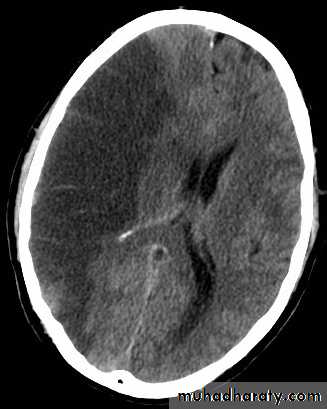

Subarachnoid hemorrhage

causesdue to ruptured aneurysm over 90 % of cases spcially at the circle of Willis .

ruptured AV malformation .

trauma .

CT finding

hyper density is seen within the SAS ( hyperdense sulci , being filled with clotted blood)

opacified inter hemispheric fissure ( become white & more dense )

opacification of the falx cerebri .

SAH

White sulciOpacified IHF